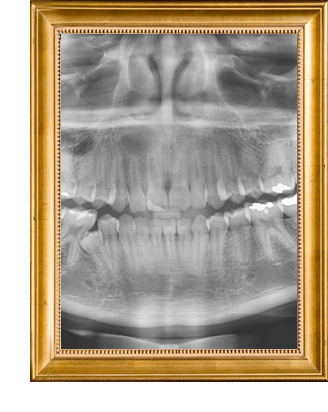

Antes de qualquer extração o Dr. Leonardo vai avaliar sua saúde bucal e realizar rx dos dentes a serem extraídos ou ainda pedir exames complementares para avaliar o tamanho, formato e posição dos dentes.